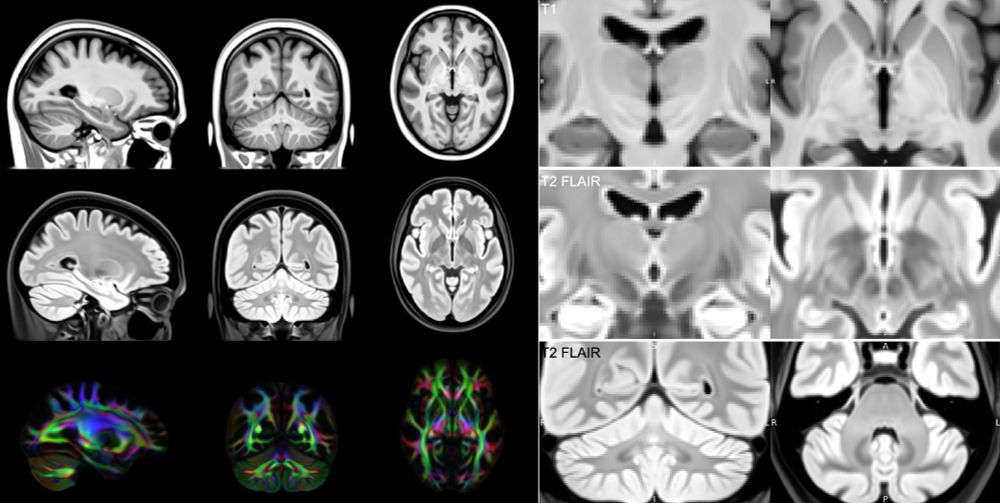

New paper in Imaging Neuroscience by Christoph Arthofer, Frederik J. Lange, et al:

Internally consistent and fully unbiased multimodal MRI brain template construction from UK Biobank: Oxford-MM

doi.org/10.1162/imag...